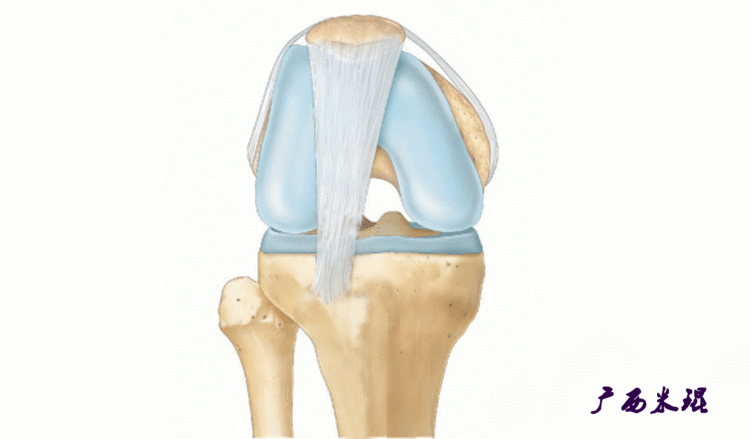

说到髌骨脱位,首先就要了解髌骨,髌骨是人体最大的籽骨,倒三角状位于膝关节前方,它的上缘与股四头肌腱相连,下缘通过髌韧带止于胫骨结节上,两侧为股四头肌扩张部,髌骨后方的凸面为光滑的关节面,与股骨下端内外髁之间的滑车凹面关节面形成关节。尽管股四头肌中的股直肌、股中间肌、股外侧肌的作用方向与髌韧带不在一条直线上,髌骨有向外突出的倾向,但因股内侧肌有向内上方牵拉作用力而使髌骨维持在正常位置。